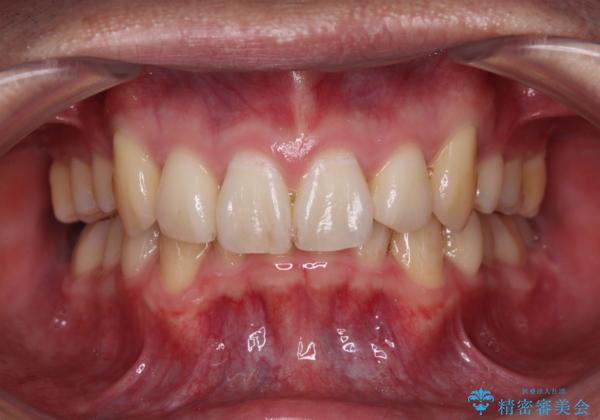

- 八重歯を気にして来院された患者様です。

顕著な上顎の八重歯とディープバイトであったため、上顎の左右第一小臼歯を抜歯することとしました。

犬歯歯根の位置や奥歯の咬み合わせから、ワイヤー装置での治療を強くおすすめいたしましたが、ご本人の強い希望により、妥協的な仕上がりとなることを了解いただき、インビザラインにて矯正治療を行うこととしました。